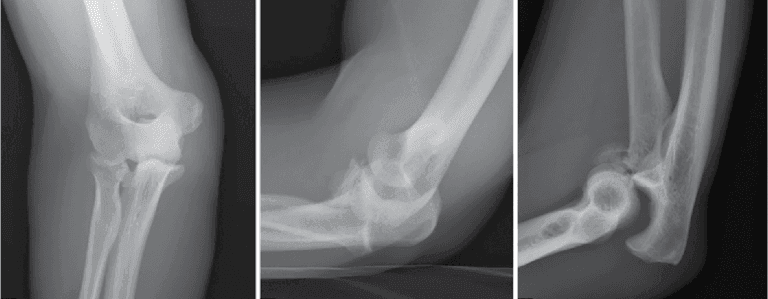

- Radiographs (X-rays):

- Essential for evaluating the alignment of the ulnohumeral and radiocapitellar joints.

- Look for coronoid fractures.

- Both pre-reduction (before the bones are set) and post-reduction films are needed.

- Additional wrist and forearm X-rays may be necessary.